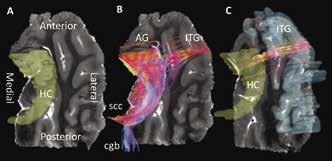

Figure 2A shows a coronal slice of the MD image compared to the same image overlaid with all reconstructed streamlines within it. When comparing the streamlines shown in Figure 2A and the ROIs in Figure 2B, it can be determined that streamlines seem to be less dense in grey matter regions than in white matter regions. Additionally, it is shown that white matter regions appear to be mostly arranged in in the medial/lateral orientation. In Figure 3B at the tail, or fimbria, of the posterior HC, axonal projections join the selenium of the corpus callosum (scc) and a telencephalic white matter tract, the cingulum bundle (cgb). This result verifies the previously known connection of the HC to the cgb and supports the fact that DTI can accurately contribute to the discovery of grey matter interconnectivity within the TL [3].

Figure 2: (A) Coronal view of one of the TL MD maps compared to the same image showing all generated streamlines from reconstruction by computational detection and tracing of the FA vector in each voxel in the image. Streamline colors represent its 3D direction in space, with red=lateral/ medial, green=superior/inferior, and blue=anterior/posterior. Intermediate colors represent a combination of two directions. (B) Coronal and transverse views showing the three-dimensional region of interest maps drawn on the DTI image. Here the superior, medial, and inferior temporal gyri are shown (labeled as STG, MTG, and ITG), as well as the parahippocampal gyrus (PHG), subiculum (SB), and hippocampus (HC).

Figure 3B illustrates extra- and intrahippocampal streamlines were successfully reconstructed from the hippocampus ROI shown in Figure 3A. Furthermore, this approach demonstrates for the first time that visual representations of both white and grey matter connectivity in the TL can be probed using tractography. The visualization of neuronal connections in Figure 3B and 3C show a precise location for streamline termination as well as provide a qualitative understanding of their arrangement. In Figure 3B, at the anterior end of the HC, efferent neurons connect to two grey matter structures: the AG and ITG. Connections to the AG are few in number, but highly organized. Streamlines extending to the ITG terminate on both medial and lateral edges of an anterior segment of the gyrus. Conversely, as shown in Figure 3C, efferent connections from the ITG appear to fan out within the HC.

Figure 3: (A) Transverse view of one of the TL MD maps with the hippocampus delineated by a 3D ROI. (B) Result of streamline reconstruction by computational detection and tracing of the FA vector in each voxel in the HC ROI. Streamlines within, extending from, and ending in the HC are shown. Streamline colors represent its 3D direction in space, with red=lateral/medial, green=superior/ inferior, and blue=anterior/posterior. Intermediate colors represent a combination of two directions. Tractography reveals four bundles of neurons extending from the HC. At the anterior HC, streamlines connect to the ITG and AG while at the posterior HC, streamlines join the cingulum bundle (cgb) and selenium of the corpus callosum (scc). (C) Isolated streamlines seeded (beginning) in the ITC ROI and ending in the HC ROI.